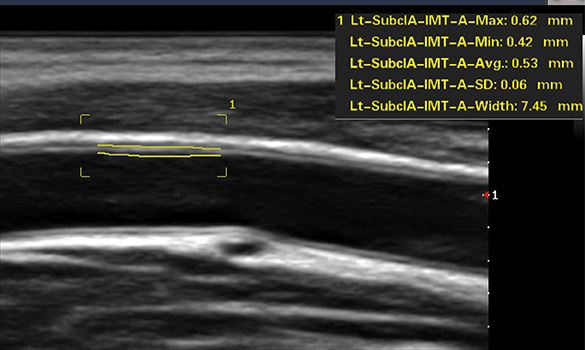

Auto IMT

Automatically calculates intima-media thickness for fast, consistent vascular assessment.